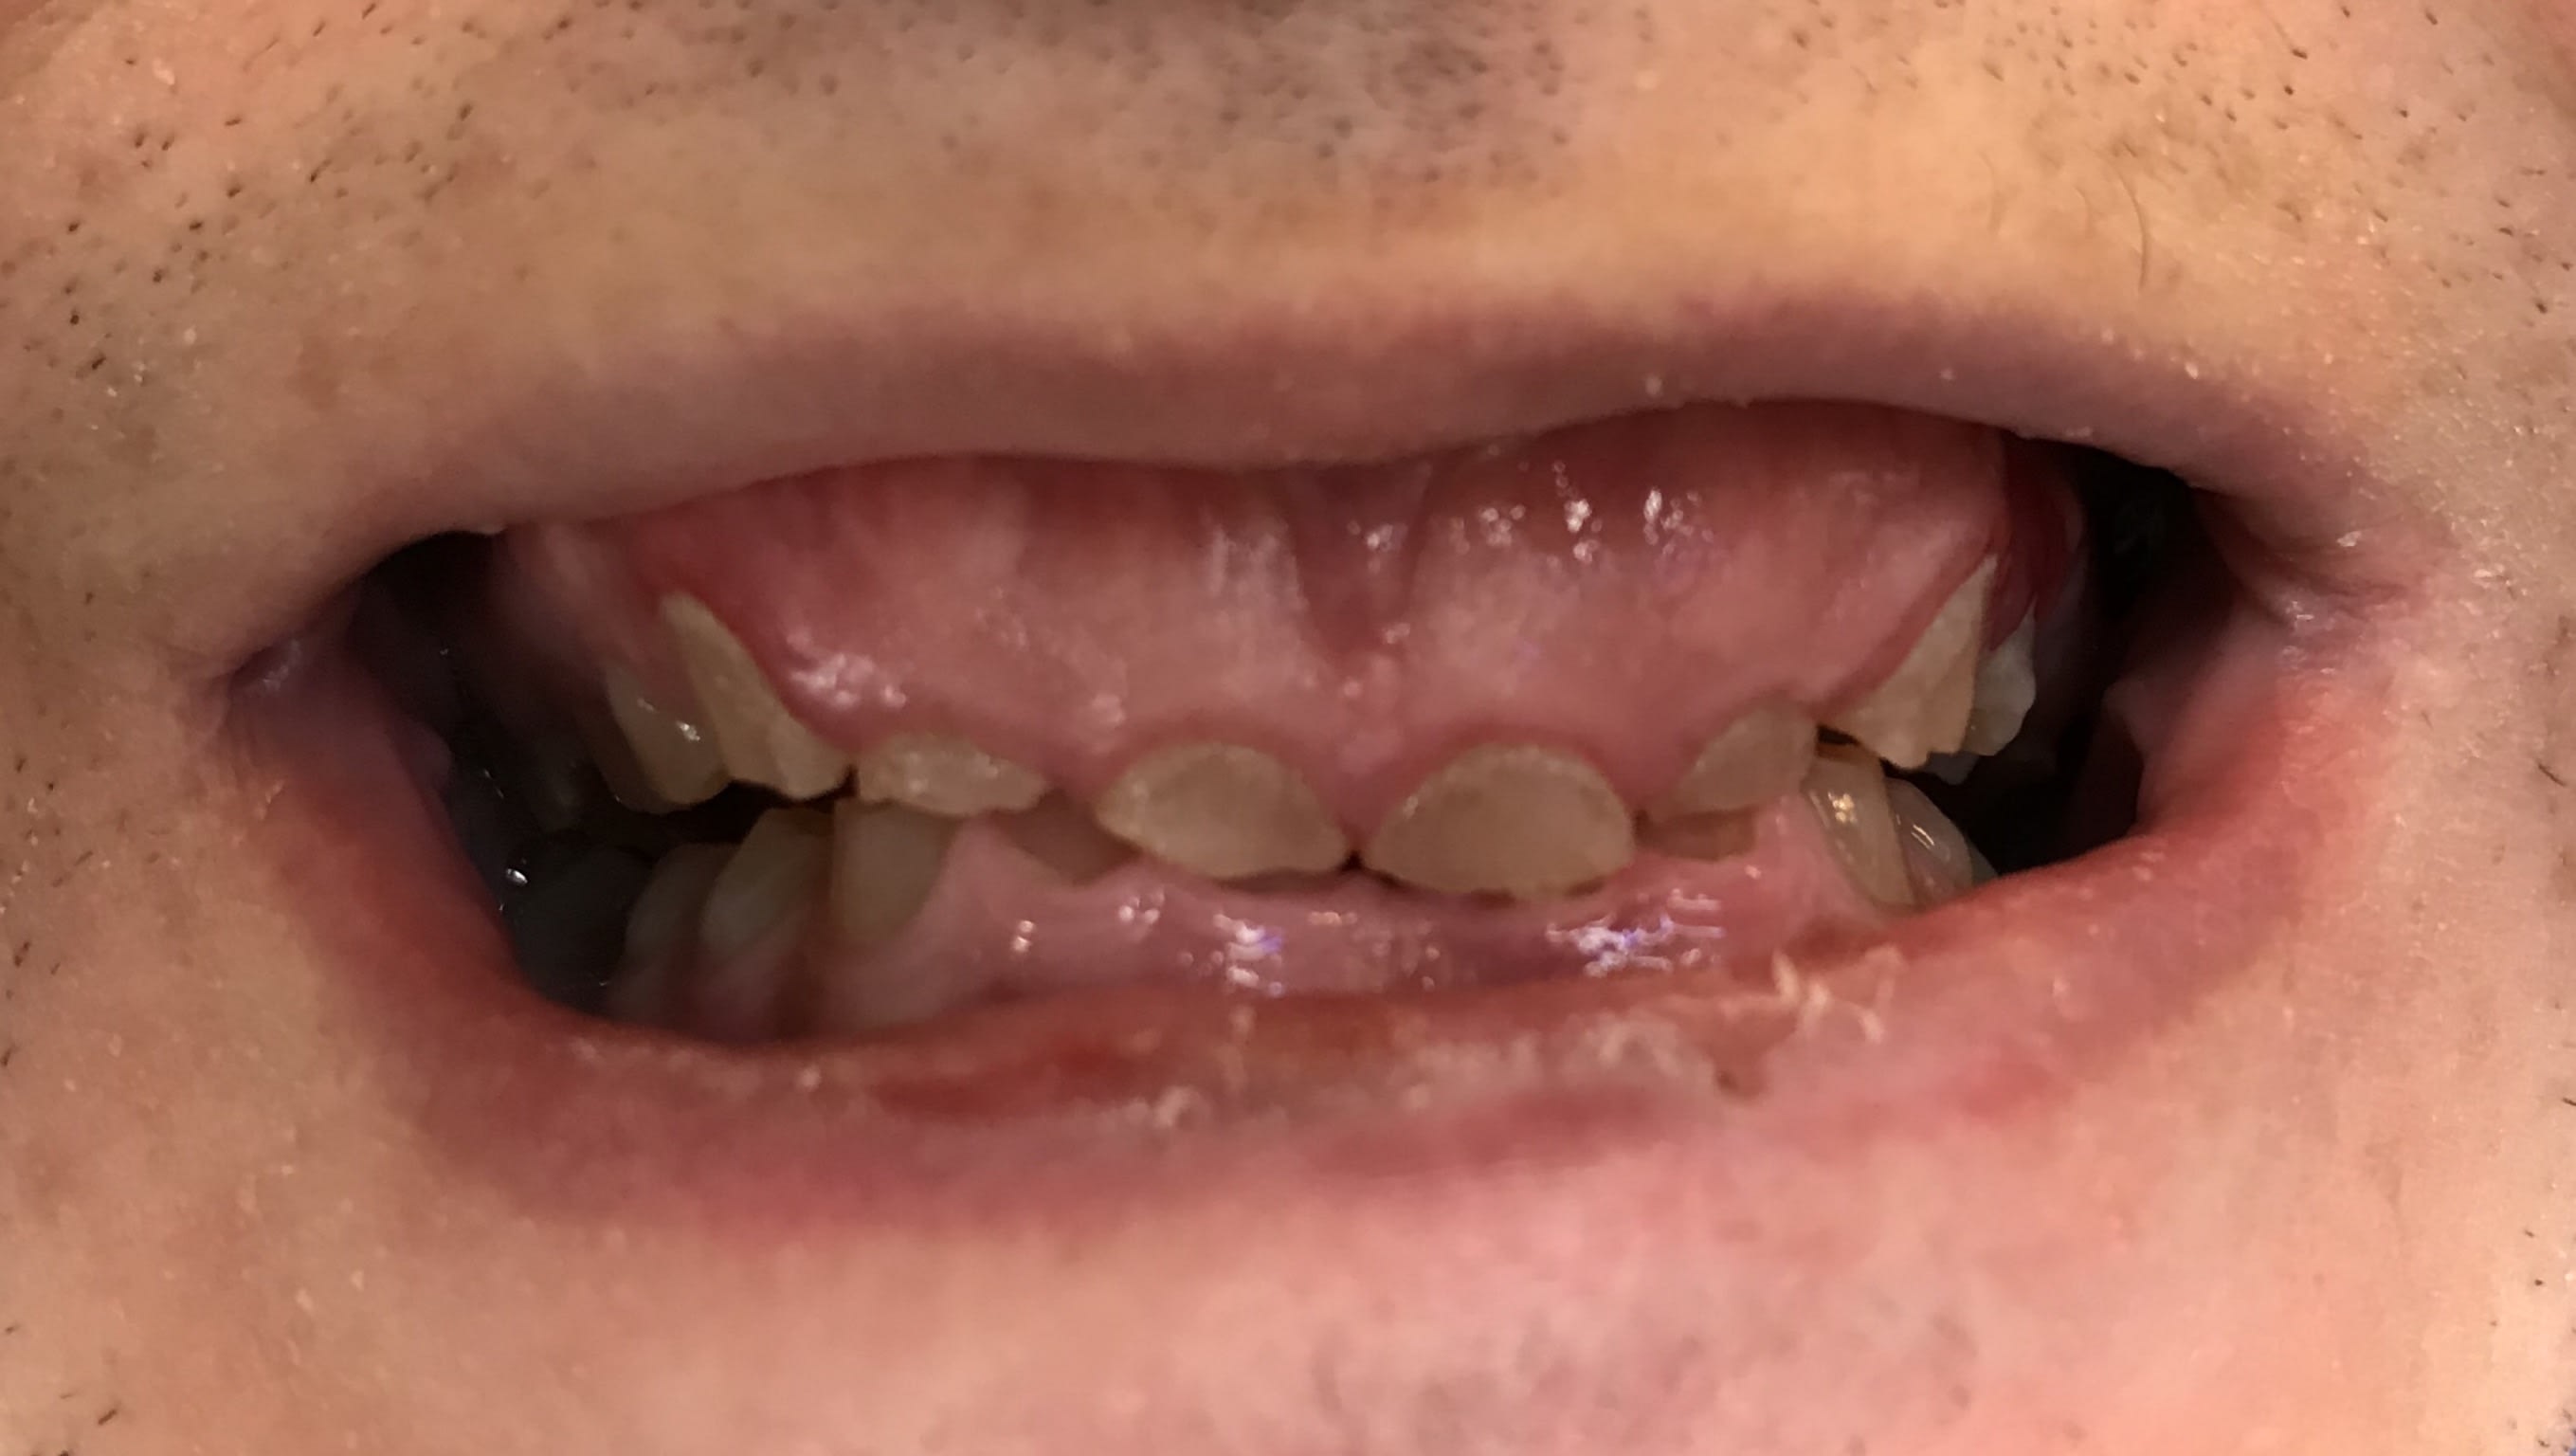

Photos

A82f03fd 2d91 4ef1 97ca f3eb47c7b10d m438gf - Eugenol

780581f7 855e 4bfa 8613 66d779c84307 rrwohx - Eugenol